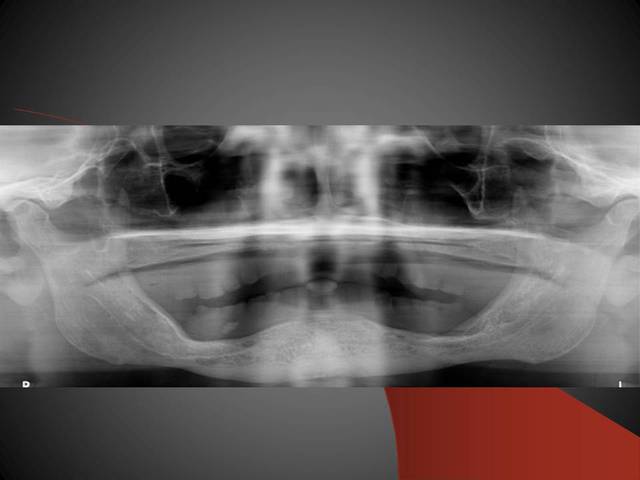

3ème photo: radio d´un patient âgé de 73 ans qui souhaitait avoir des dents fixées.Comme on l´observe il n a plus de place après les foramines mentales.Nous avons donc utilisé juste l´os interforaminal. Nous avons suivi le concept du prof. Nentwig qui consiste à pouvoir ajouter 2 dents dans chaque quadrant dans la mandibule.

Mon guide était l´ancienne prothèse avec laquelle j´ai fait un OPG en plaçant un trombone metallique entre les dents 4 et 5 dans la prothèse, ainsi j ai pu utiliser la prothèse comme un guide pour éviter un problème avec la zone foraminale....